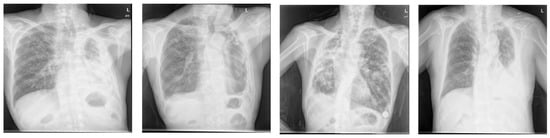

Figure 8.

Chest X-ray and lung segmentation results of patients with pneumothorax (a,b) and pleural effusion (c,d).

As observed in the aforementioned results, the proposed method showed good segmentation performance for chest X-ray images of normal lung shapes. However, deep learning-based methods, including the proposed method, exhibit poor segmentation performance for chest X-ray images with deformed lung shapes or lesions that obscure the border of heart and diaphragm, which was demonstrated in a previous study [4]. For instance, the chest X-rays of patients with pleural effusion do not have normal lung contours due to abnormal fluid accumulation. Moreover, in the chest X-ray image of a patient with pneumothorax, the presence of several holes in the lung alters the lung shape. Thus, a low segmentation performance is observed when chest X-ray images of these abnormal lung regions are used for evaluation (see Figure 8). To address such rare cases and improve the generalization capability of deep learning-based approaches, additional training datasets from such cases need to be used.